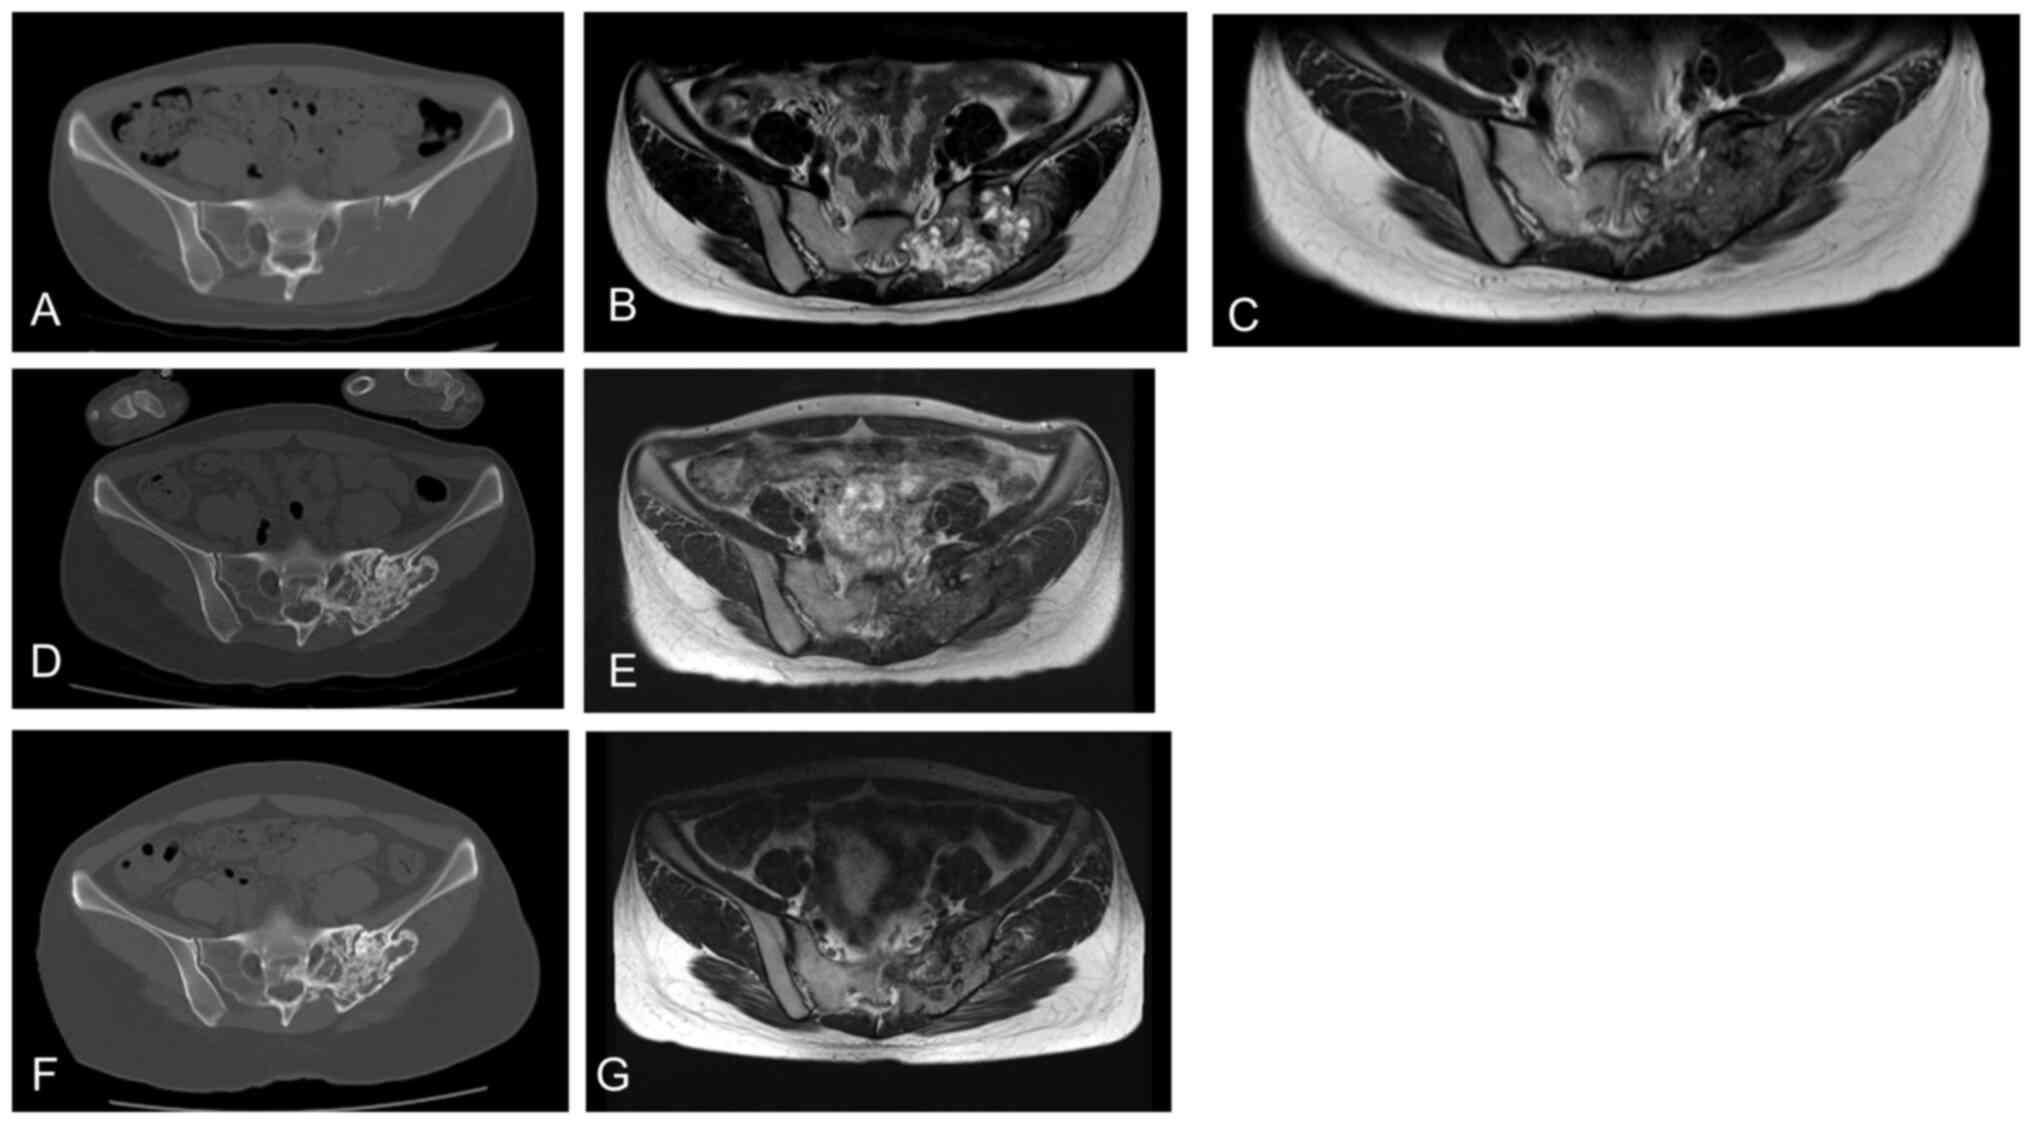

A 25-year-old woman with sacral GCTB presented with severe pain (NRS=9) and numbness in her left buttocks and lower limbs. CT imaging revealed a huge mass in the sacrum with cortical destruction and extensive soft tissue involvement (Fig. 3A). MRI revealed a large tumor in the sacrum with high intensity on T2-weighted images (Fig. 3B). The patient underwent standard denosumab therapy. Her pain decreased (NRS=2) after 1 week and disappeared after 2 weeks. Five months later, MRI revealed remarkable tumor shrinkage (Fig. 3C). The patient showed stable disease over the next 2 years, with remarkable sclerosis of the lytic lesions (Fig. 3D). After 8-weekly treatment of denosumab for 6 months, the patient achieved stable disease (Fig. 3E). She then received 12-weekly denosumab therapy. At the last follow-up, she continued to show stable disease (Fig. 3F, G).

A 25-year-old woman with sacral GCTB. (A) A huge mass in the sacrum with cortical destruction and extensive soft tissue involvement was observed on CT. (B) MR imaging revealed a large tumor in the sacrum with high intensity in T2-weighted images. (C) Five months after the start of denosumab treatment, MR imaging showed remarkable shrinkage of the tumor. (D) Stable disease was observed over the next 2 years, with remarkable sclerosis of the lytic lesions. (E) The following 8-weekly treatment of denosumab for 6 months resulted in stable disease; hence, a 12-weekly denosumab treatment was provided. (F) At the last follow-up, the patient showed stable disease as shown in CT. (G) At the last follow-up, the patient showed stable disease as shown in MRI. GCTB, giant cell tumor of bone; CT, computed tomography; MR, magnetic resonance.